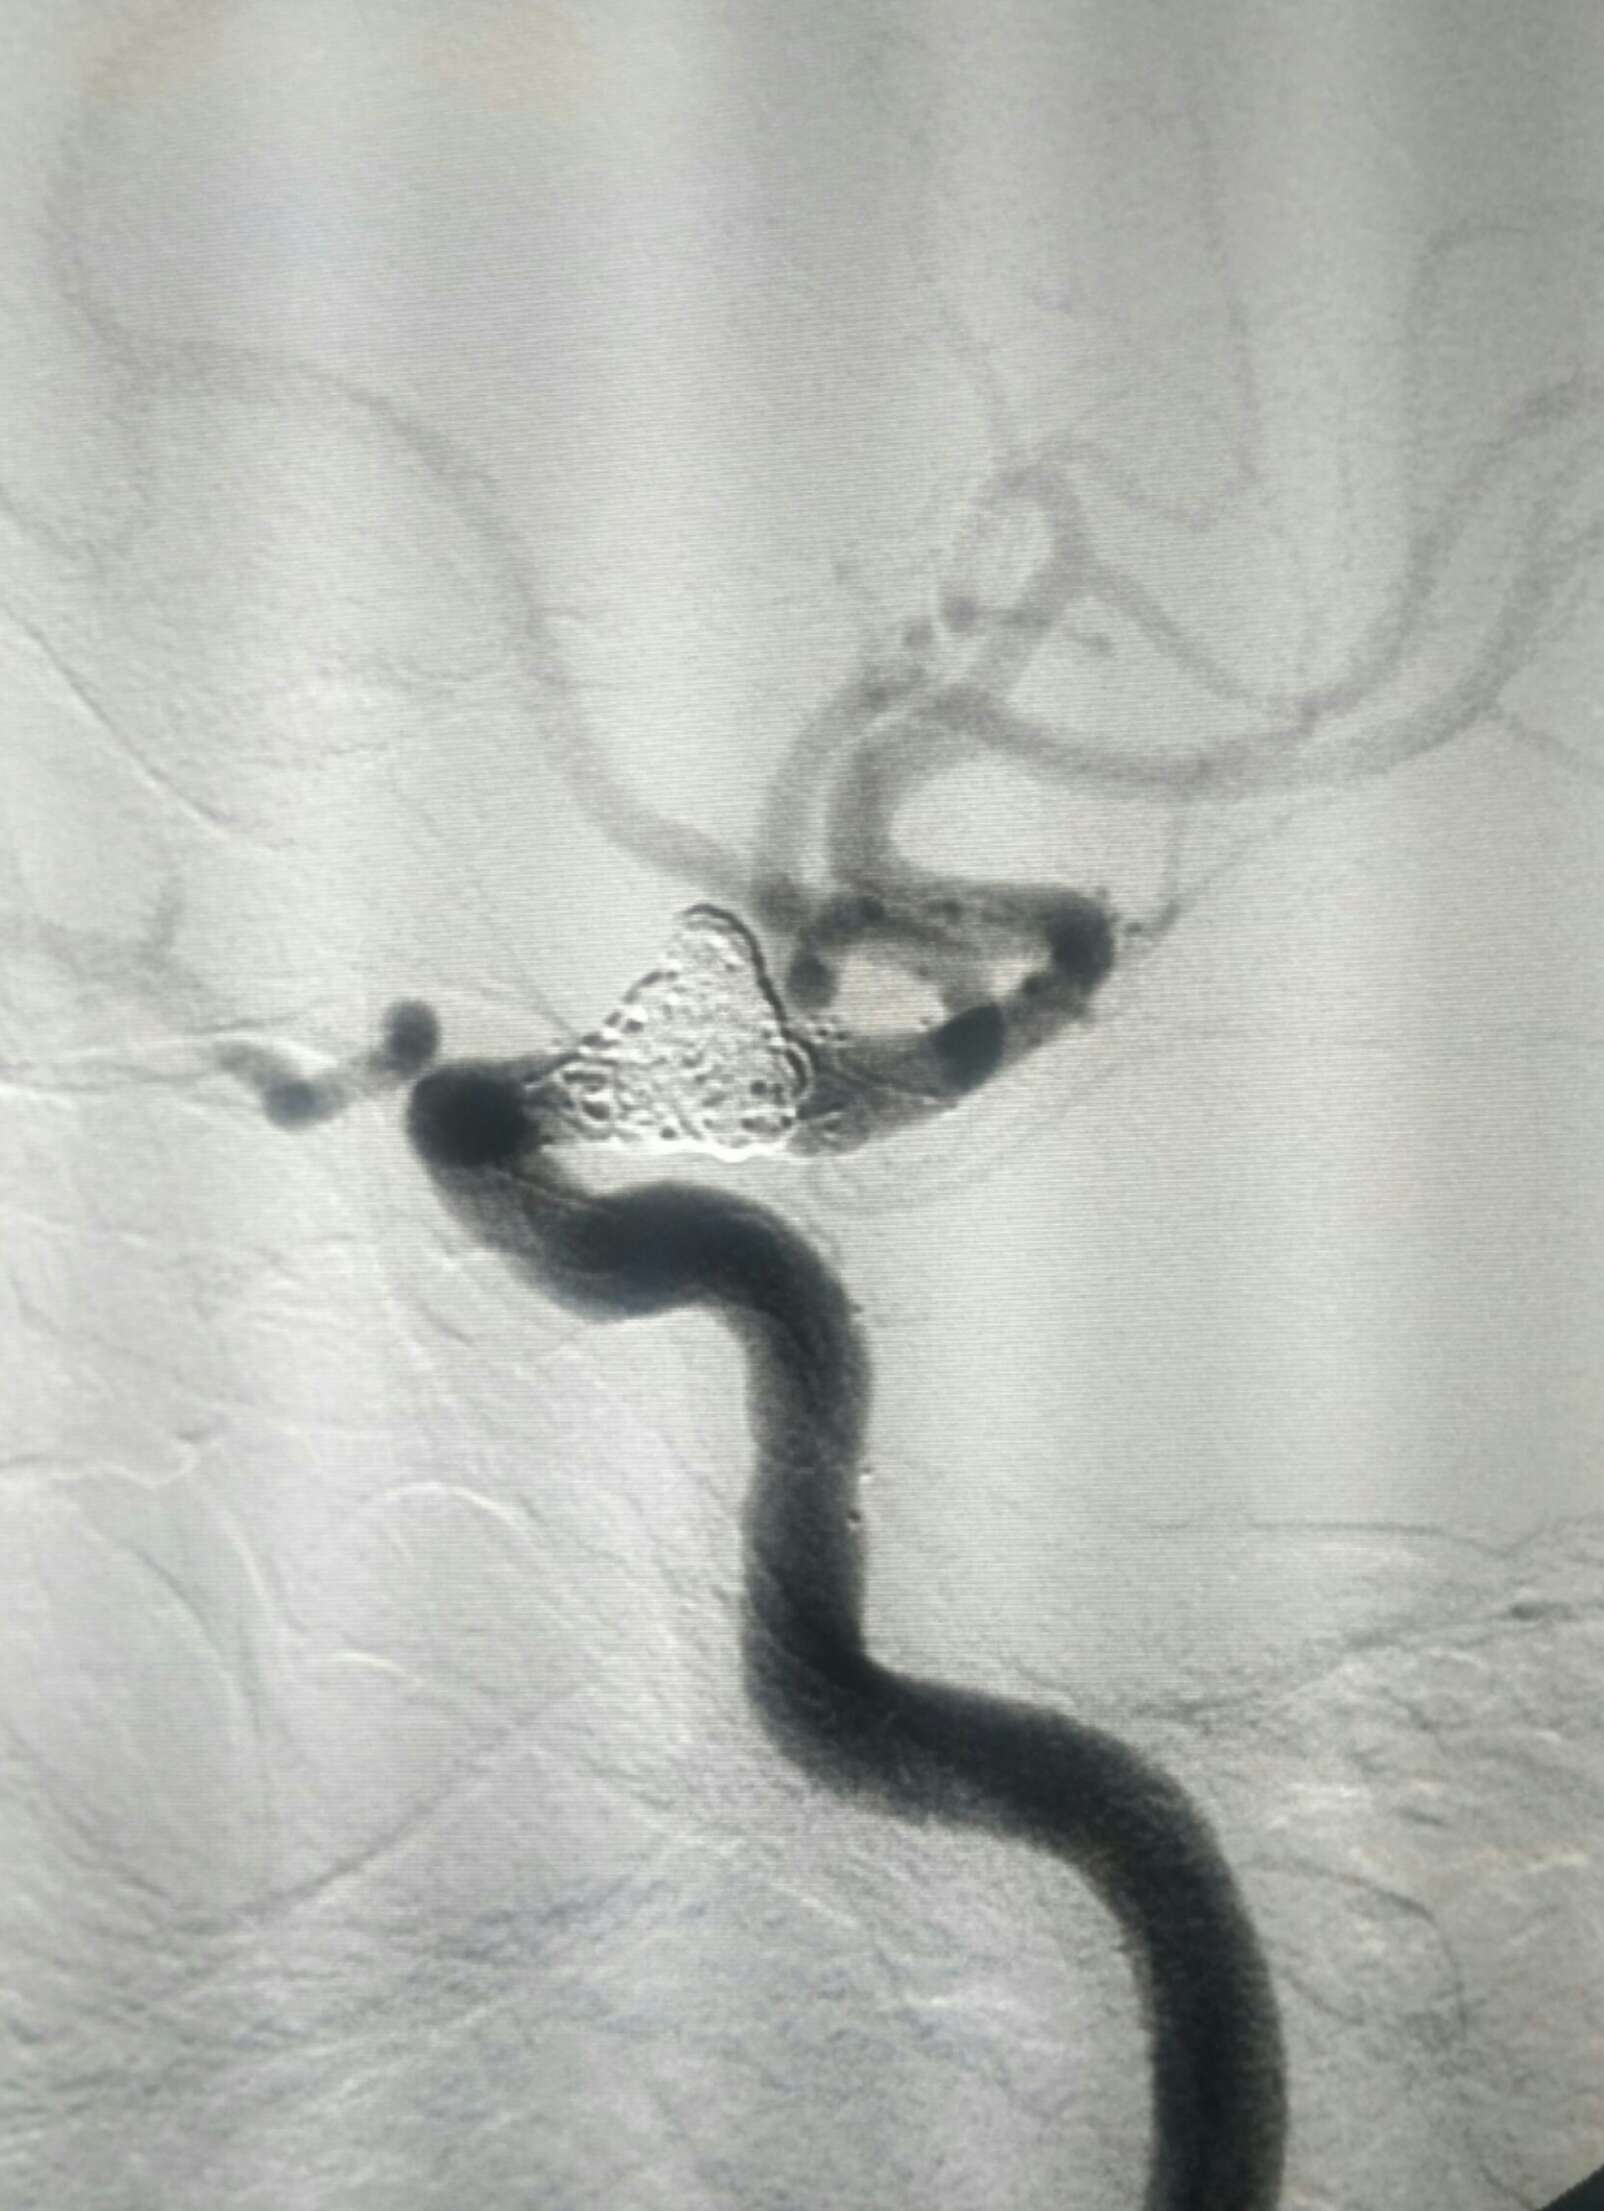

手术方案:双支架+弹簧圈+打补定致密栓塞

,短期复查拼人品!希望治愈,如果复发考虑血流导向装置或者闭塞颈内动脉!😡

栓塞工作角度33/-28影像满意

正位像栓塞影像满意

侧位像满意

顺利收工😂